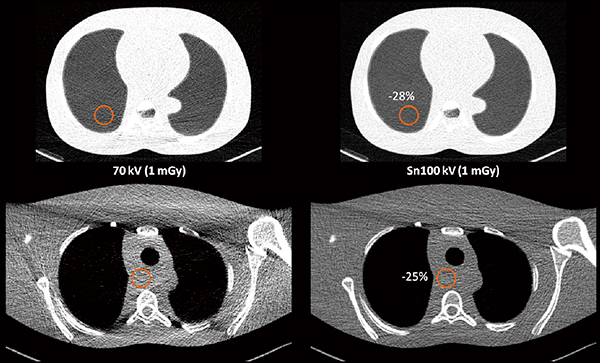

一方で,同等の照射線量(フォトン数)であればノイズ量もほぼ同等になることが漠然と期待されるが,Tin filterを通したX線スペクトルは,その形状のユニークさによってノイズ量も特異的な性質を示す。直径300mmの水ファントムに対して同等の照射線量で70kVとSn100kVのノイズ量をNPSによって比較した場合,Sn100kVのノイズ量は70kVのわずか48%であり,70kVに強度5のADMIREを適用したノイズ量よりもやや低い値を示した(図2 b)。Tin filterによって低線量でも低ノイズの画質が得られ,高い被ばく低減効果が期待できることを示している(図3)。

図3 Sn100kVによる肺の超低線量CT(1mGy)のファントム画像